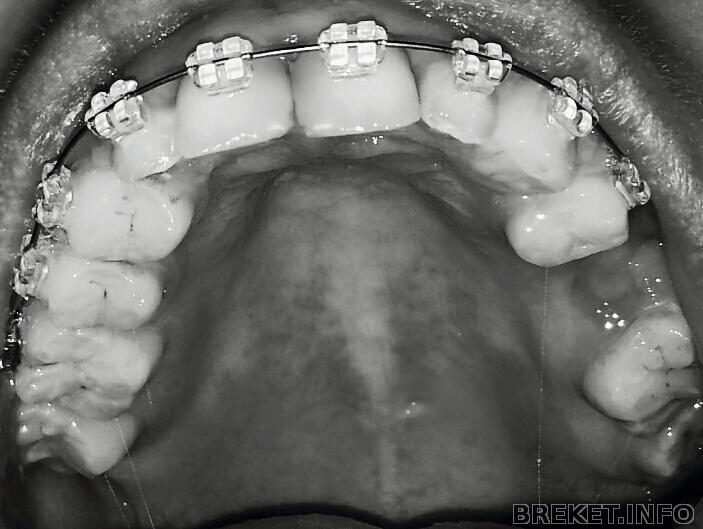

Вообщем,всем привет,моим брекетам уже 2 недели

брекеты у меня безлигатурные